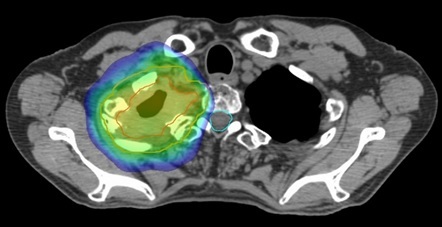

中咽頭がん。手術では取り切れなくても放射線治療は可能。

IMRTは照射したい場所に沿って照射できる技術。

従来法に比べ周囲の正常臓器・組織を避けて照射できる。

これにより有害事象(副作用)の低減が図れる。